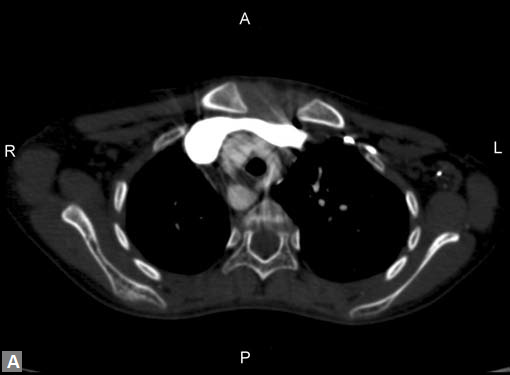

Filling defects (Figs 16A and B) may be seen in main

pulmonary artery (MPA), left pulmonary artery (LPA) and

right pulmonary artery (RPA), interlobar artery, segmental

divisions (Figs 17A and B). On occasions, detection in distal

parts of segmental divisions is difficult. This can be further

confounded by motion artifacts, non- or minimally opacified

accompanying pulmonary veins.